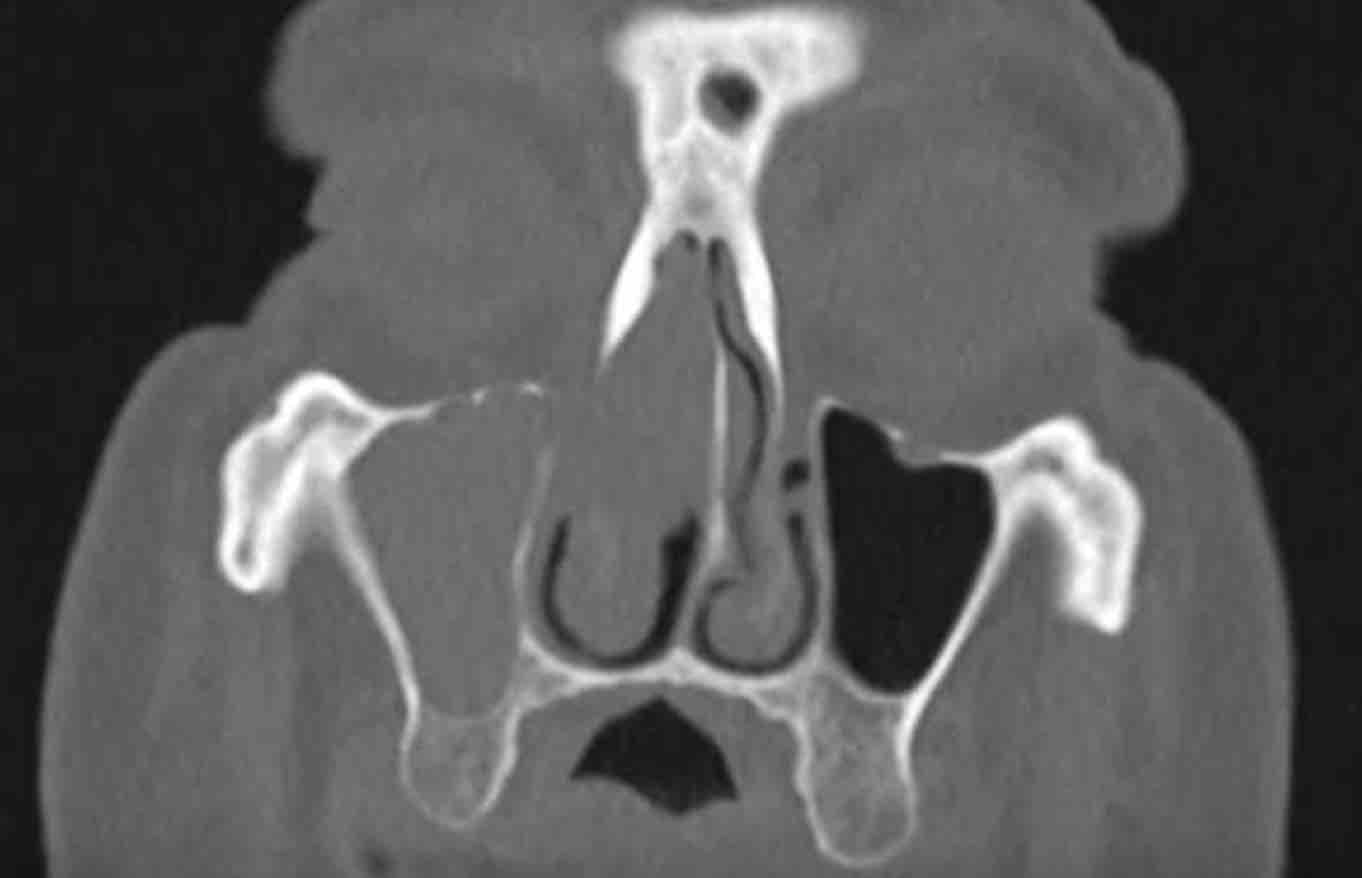

Các hình ảnh này của bệnh nhân nam 47 tuổi, có triệu chứng căng tức vùng trán.

Hãy quan sát các hình ảnh trước.

Các dấu hiệu hình ảnh là gì?

Tổn thương có kiểu giãn rộng hay phá hủy hay cả hai?

Dấu hiệu hình ảnh:

- Tổn thương giãn rộng đẩy nhãn cầu trái sang bên.

- Tổn thương có bờ rõ nét.

- Tổn thương xuất phát từ xoang trán trái.

- Thành trong hốc mắt trái (đầu mũi tên đen) và nền sọ (đầu mũi tên trắng) bị mỏng đi, nhưng không có phá hủy xương.

MRI được thực hiện để xác nhận chẩn đoán nhiều khả năng nhất là nang nhầy…

MRI cho thấy tổn thương giãn rộng chỉ có ngấm thuốc tương phản từ ở vùng viền ngoại vi.

Không có ngấm thuốc bên trong tổn thương.

Điều này xác nhận chẩn đoán nang nhầy.

Nang nhầy là tổn thương dạng nang chứa đầy chất nhầy.

Nang hình thành khi lỗ thông của (một phần) xoang cạnh mũi bị tắc nghẽn.